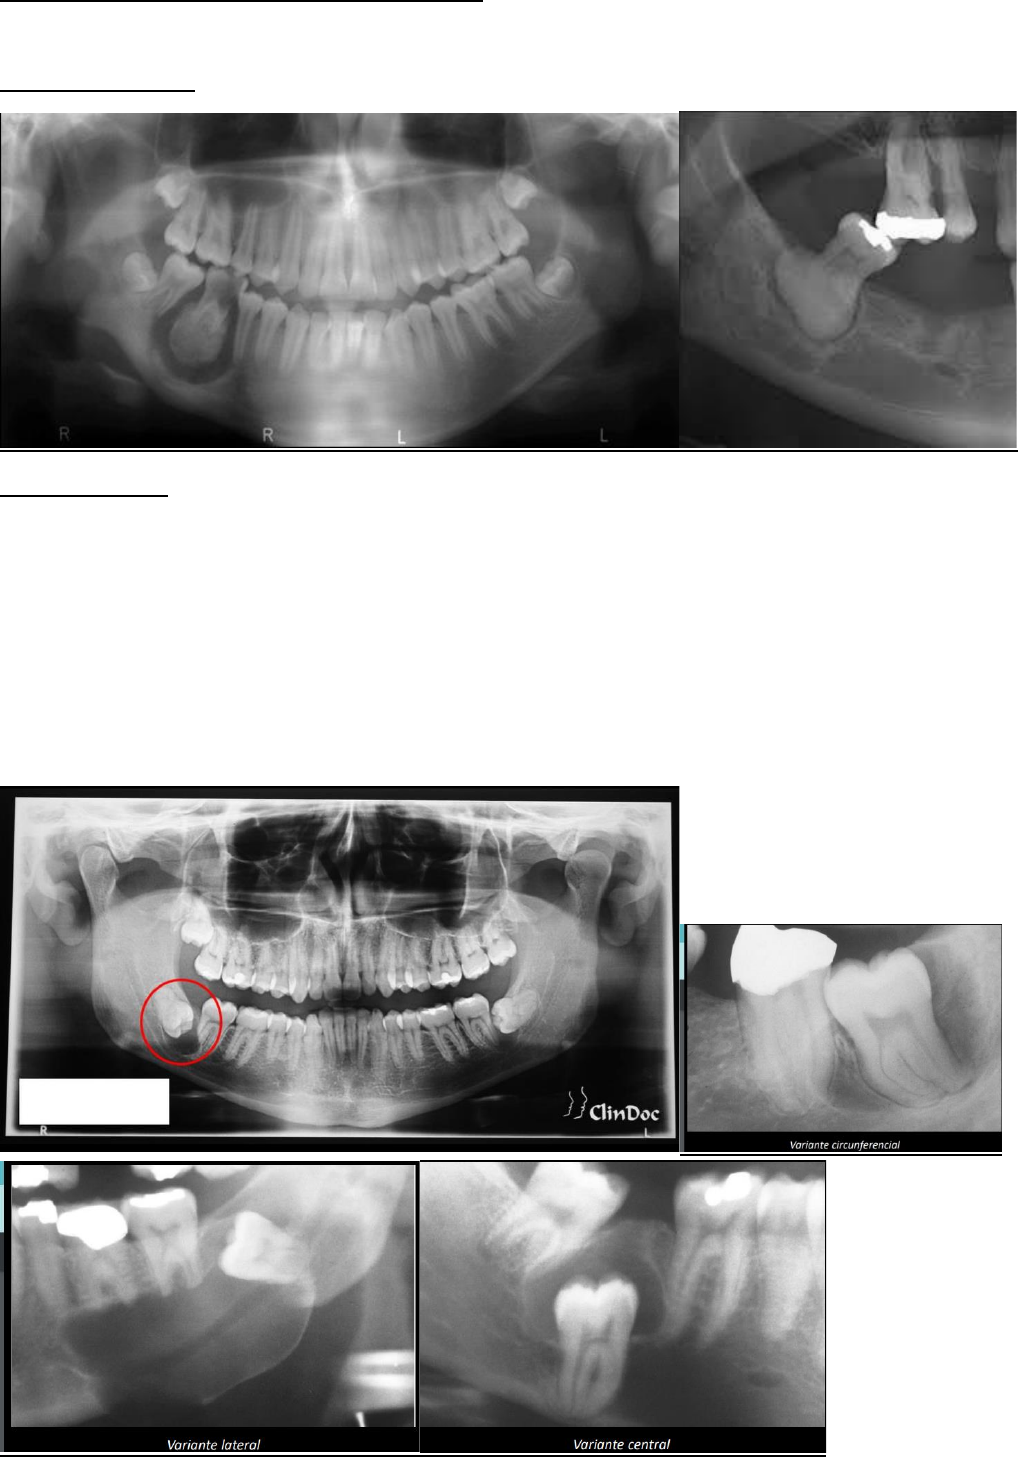

CISTO DENTIGENO

Características radiográficas

• Área radiolúcida unilocular associada à coroa de um dente incluso

• Margem bem definida, frequentemente esclerótica

• Podem deslocar o dente envolvido

• Podem fazer reabsorção dentária de dentes adjacentes

• Relação cisto-coroa: Variante Central Variante Lateral Variante Circunferencial

CISTO DE ERUPÇÃO OU DENTIGENO COM VARIANTES